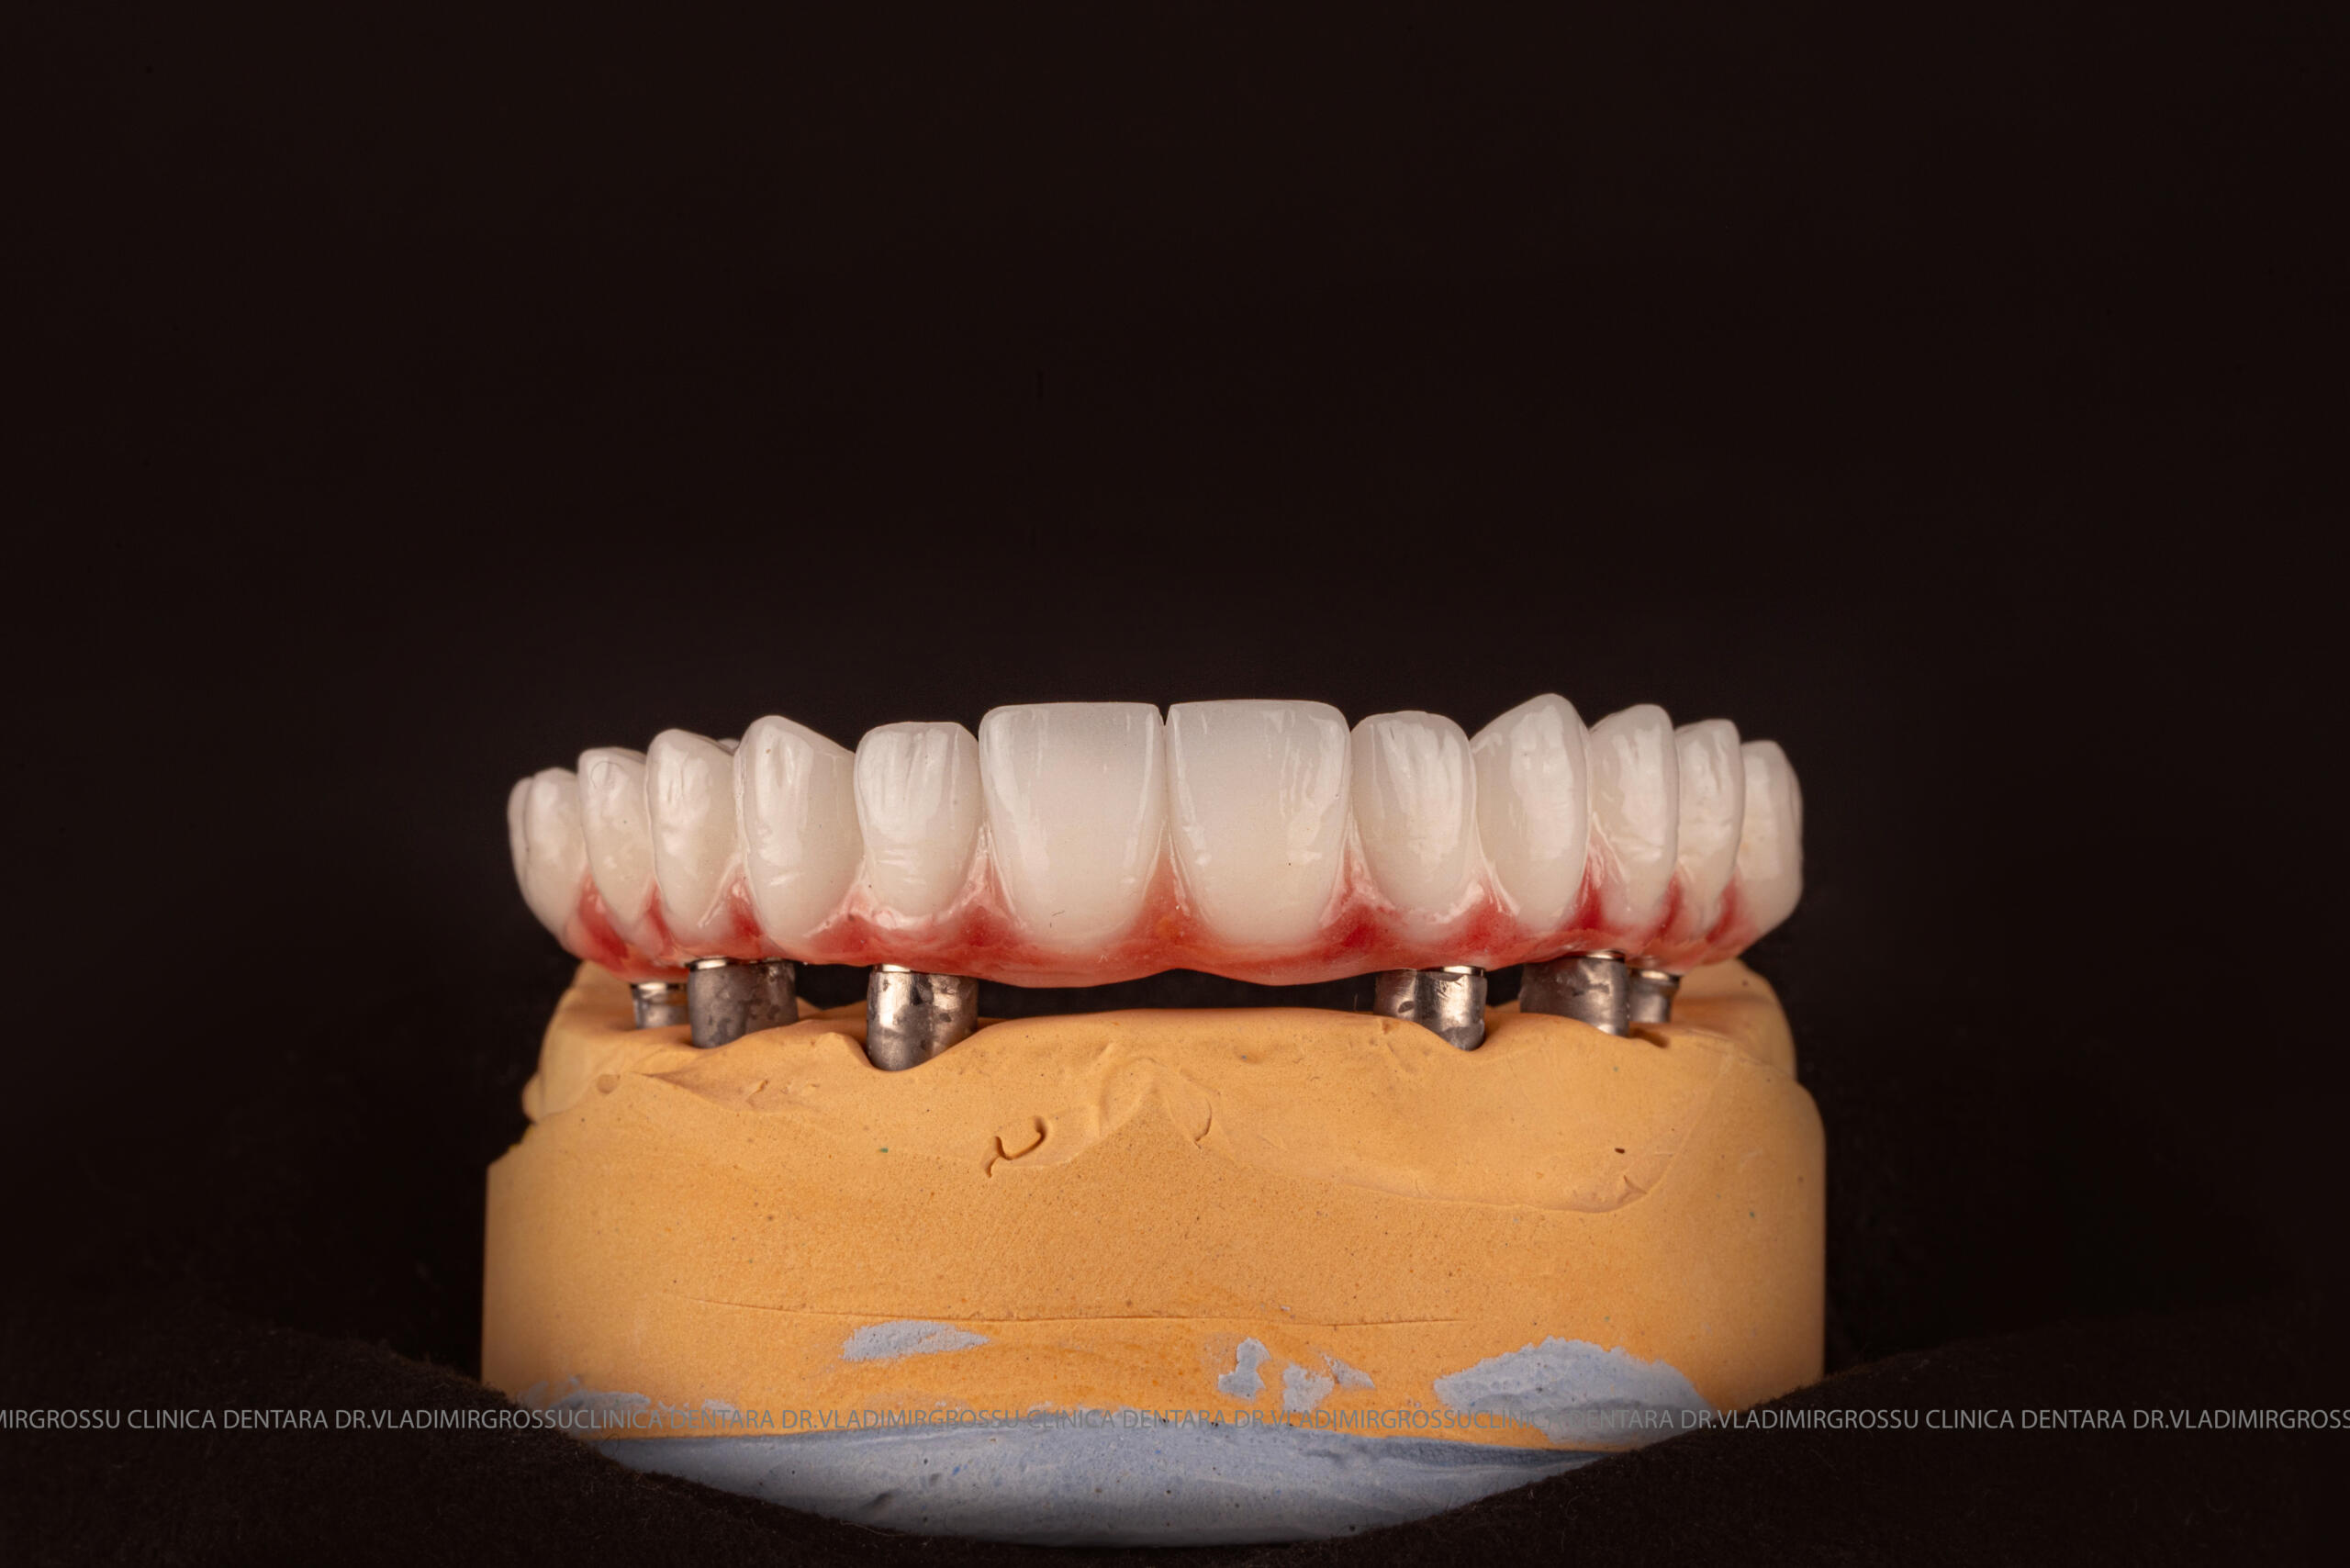

- A doua etapă are loc la aproximativ 6 luni după intervenție, când se realizează proteza definitivă, care este fixată pe implanturi prin intermediul unor piese numite multiunit-uri. Această etapă presupune lucrul la nivelul multiunit-urilor, nu direct pe implanturi, reducând astfel riscul de complicații.

- Șase abutment-uri permanente pe multiunit-uri;

- Proteză definitivă realizată din metaloceramică sau zirconiu, cu 12-14 unități (soluția recomandată).